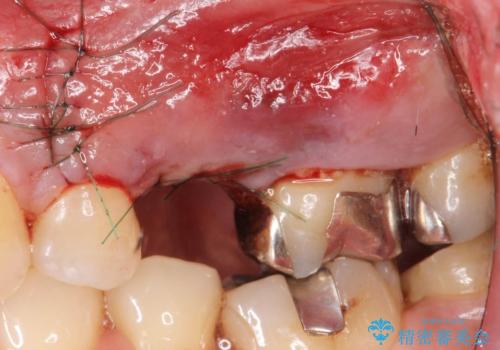

歯茎が腫れる インプラントでの治療

- 10ヶ月

- 5-10回

- 左上5/インプラント:242,000円 骨増生:55,000円 カスタムアバットメント:110,000円 インプラント用仮歯:22,000円 ジルコニアクラウン:121,000円 合計550,000円費用は治療当時の料金となります